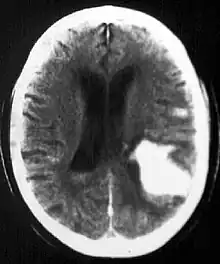

Intraparenchymal hemorrhage

Intraparenchymal hemorrhage (IPH) is one form of intracerebral bleeding in which there is bleeding within brain parenchyma. The other form is intraventricular hemorrhage (IVH).[1]

Intraparenchymal hemorrhage accounts for approximately 8-13% of all strokes and results from a wide spectrum of disorders. It is more likely to result in death or major disability than ischemic stroke or subarachnoid hemorrhage, and therefore constitutes an immediate medical emergency. Intracerebral hemorrhages and accompanying edema may disrupt or compress adjacent brain tissue, leading to neurological dysfunction. Substantial displacement of brain parenchyma may cause elevation of intracranial pressure (ICP) and potentially fatal herniation syndromes.